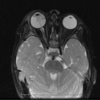

Ecchordosis Physaliphora

Cystic lesion in the prepontine cistern without enhancement or restricted diffusion extending into bone.

Absence of enhancement or restricted diffusion together with non-aggressive bony margins in this location is typical of a retroclival ecchordosis physaliphora, a notochord remnant.

Ecchordosis physaliphora is a congenital benign hamartomatous lesion derived from notochord remnants, usually located in the retroclival prepontine region, but can be found anywhere from the skull base to the sacrum.